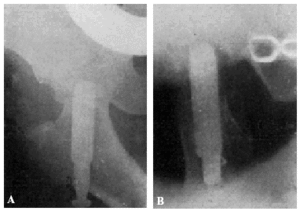

Teniendo en cuenta el mal estado general de la enferma se procede a la tracción continua, con ocho kilos de peso, mediante el procedimiento de Kirschner. A los ocho días ha mejorado extraordinariamente el estado general de la enferma, procediendo entonces a la osteosíntesis. Hay que advertir que la radiografía anteroposterior ha sido practicada antes de la completa penetración del clavo (fig. 2., A y B).

Figura 2. A: obs. núm. 8. Radiografía practicada antes de la completa penetración del clavo. Este está colocado en una posición demasiado craneal. B: Obs. núm. 8. El clavo fue colocado siguiendo la dirección del Kirschner superior. C: obs. núm. 8. El clavo se ha salido de la cabeza por su parte superior y su punta está situada a nivel de la parte superior de la caja cotiloide.